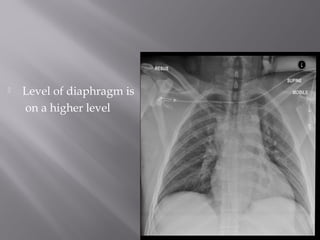

 Level of diaphragm is

on a higher level

 upper edgeof cassette just above the lung apices  arms laterally rotated  Central beam is directed towards sternal notch  FFD of 120cms.

• 35.

 Level ofdiaphragm is on a higher level